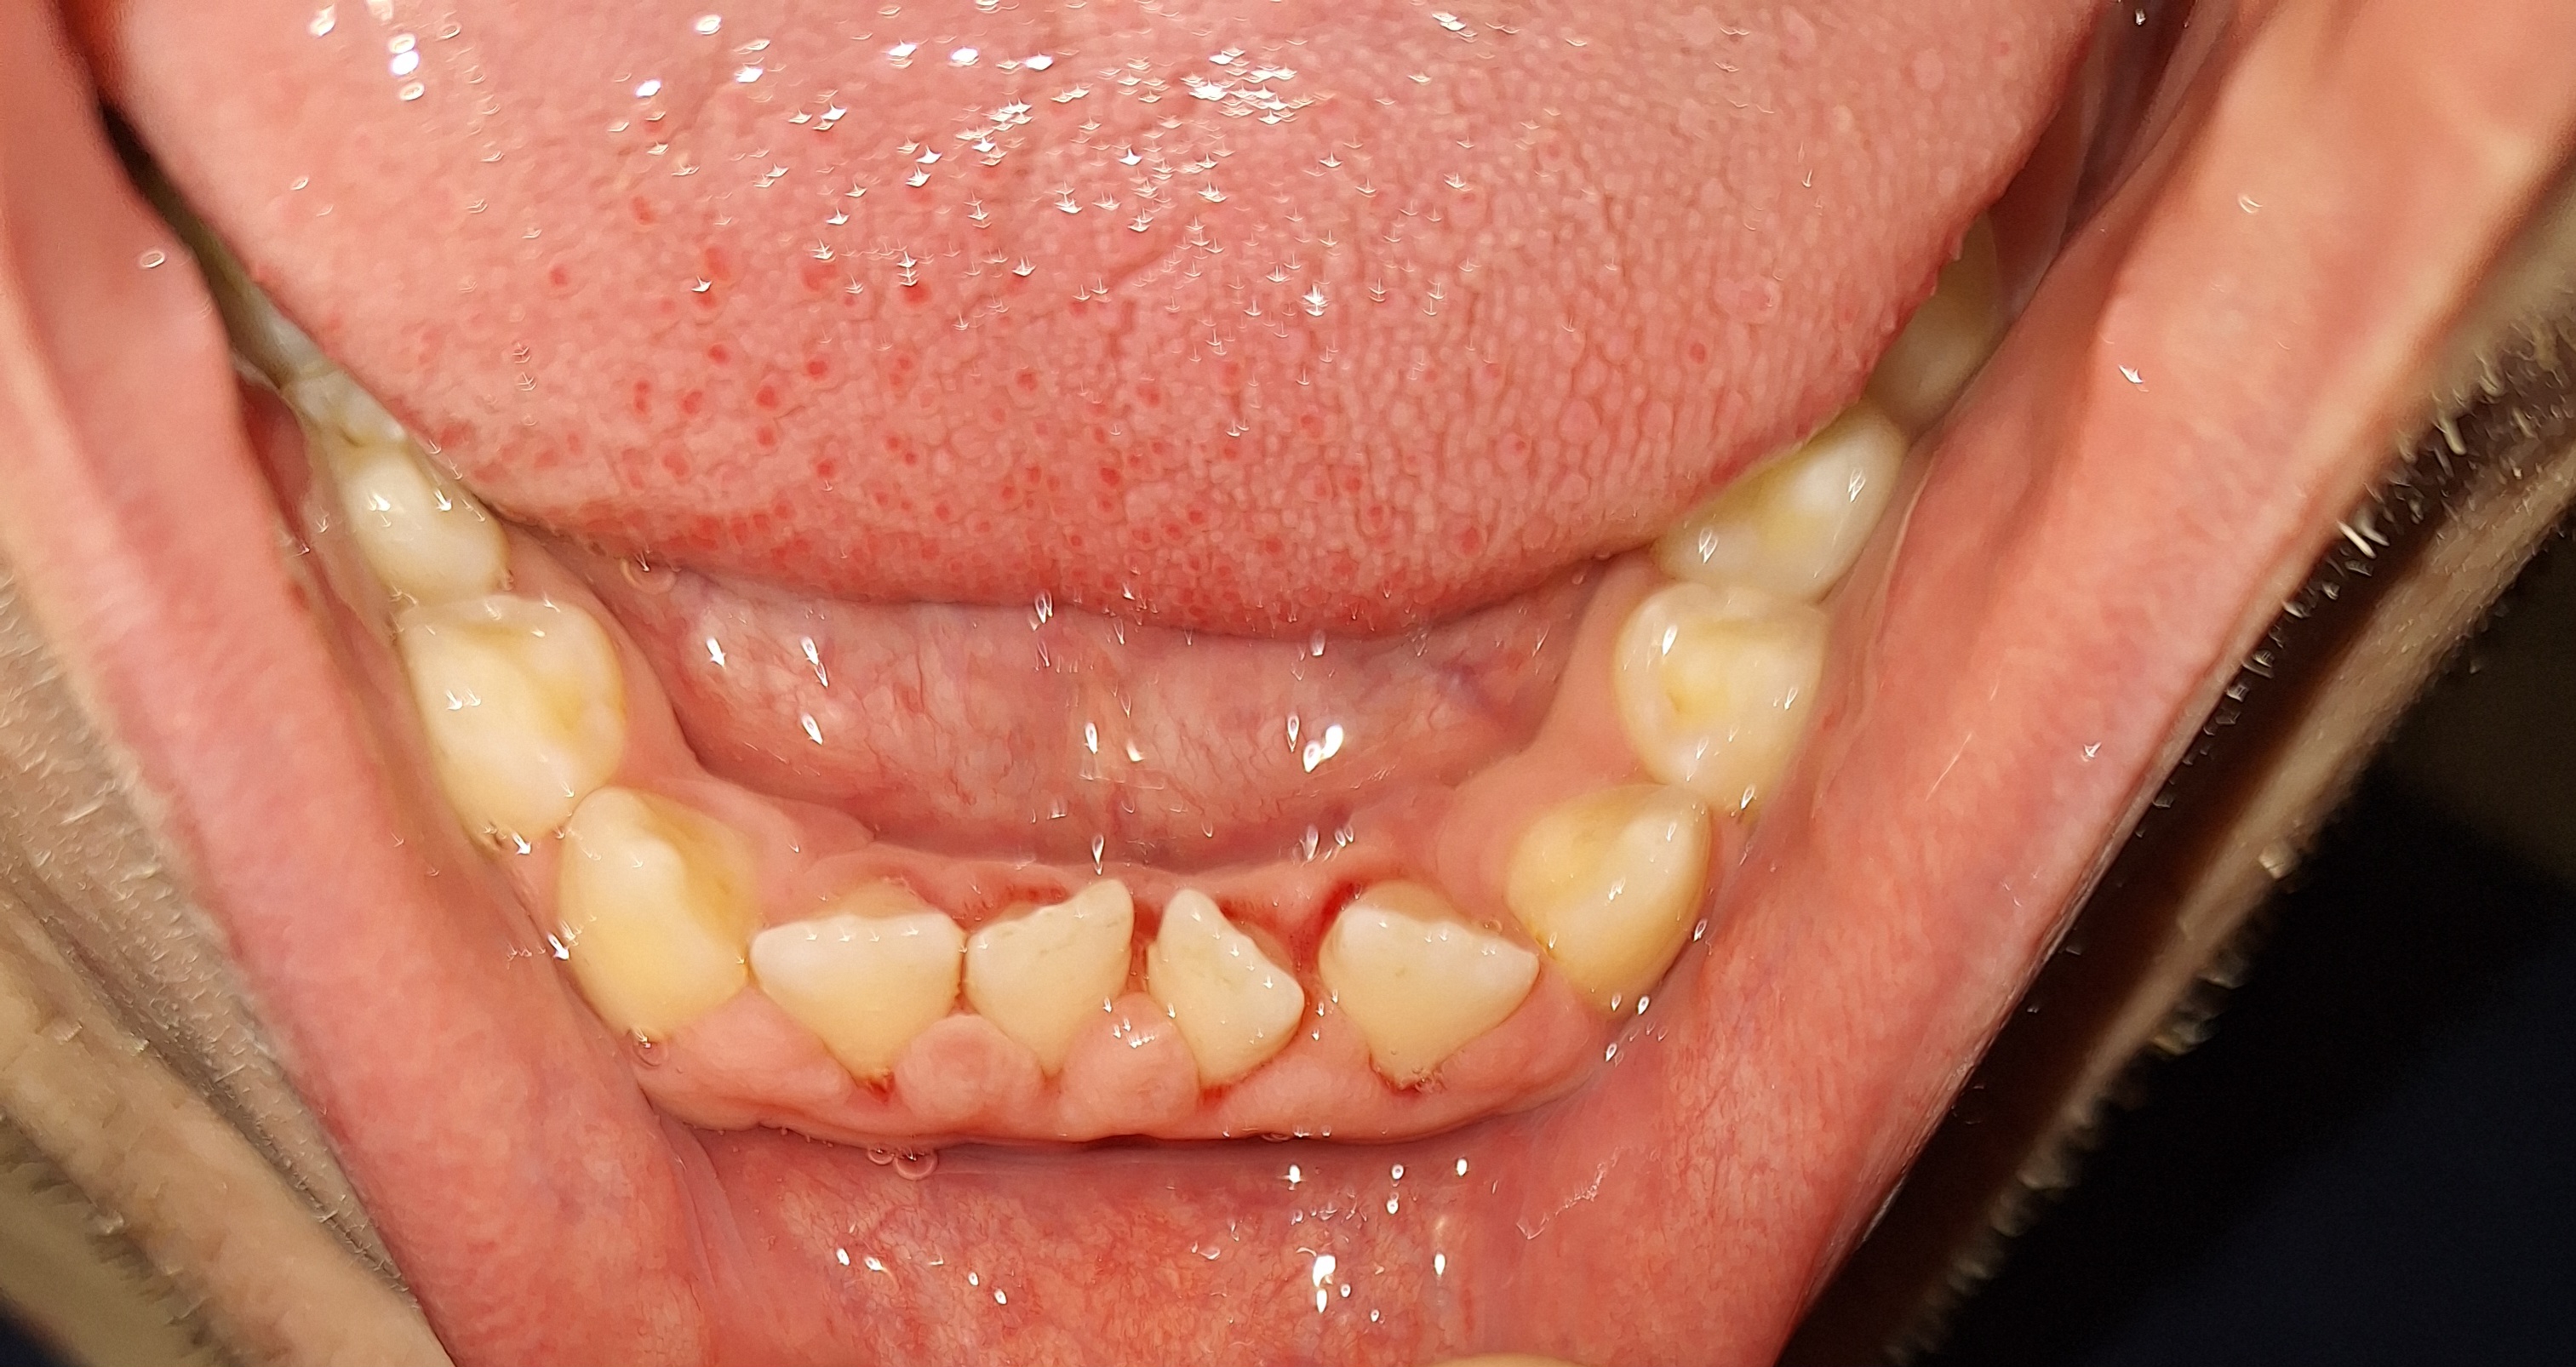

Опустились дёсны в нескольких местах, обнажились шейки зубов. Чувствительные, болят от прикосновений, могут реагировать на холодное, горячее, сладкое.

Ситуация как примерно на пик2.